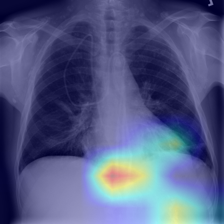

“Interactive demo that classifies chest X-rays as Pneumonia vs No Finding using a fine-tuned ResNet-18 and explains its decision with Grad-CAM heatmaps.

View on GitHub View on Streamlit